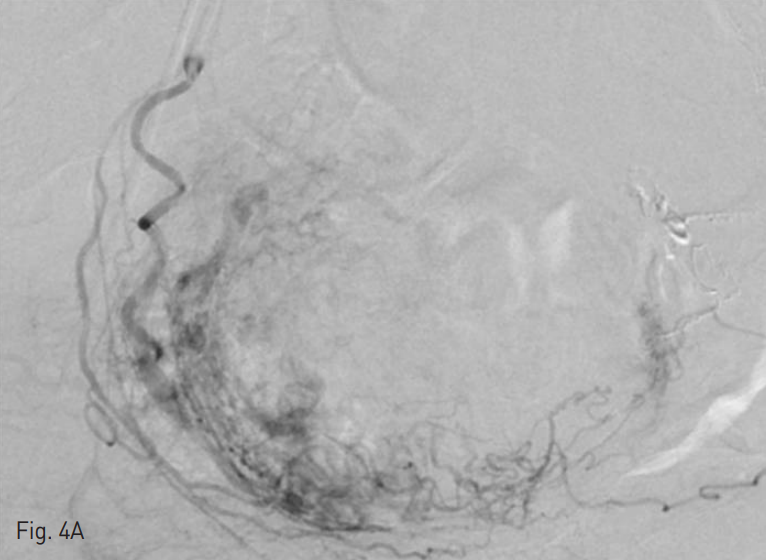

Fig. 4

Selective angiography demonstrates the uterine arteriovenous malformation fed by both uterine arteries (A~B) and multiple fine branches from left vesical artery (C) and left obturator artery (D).